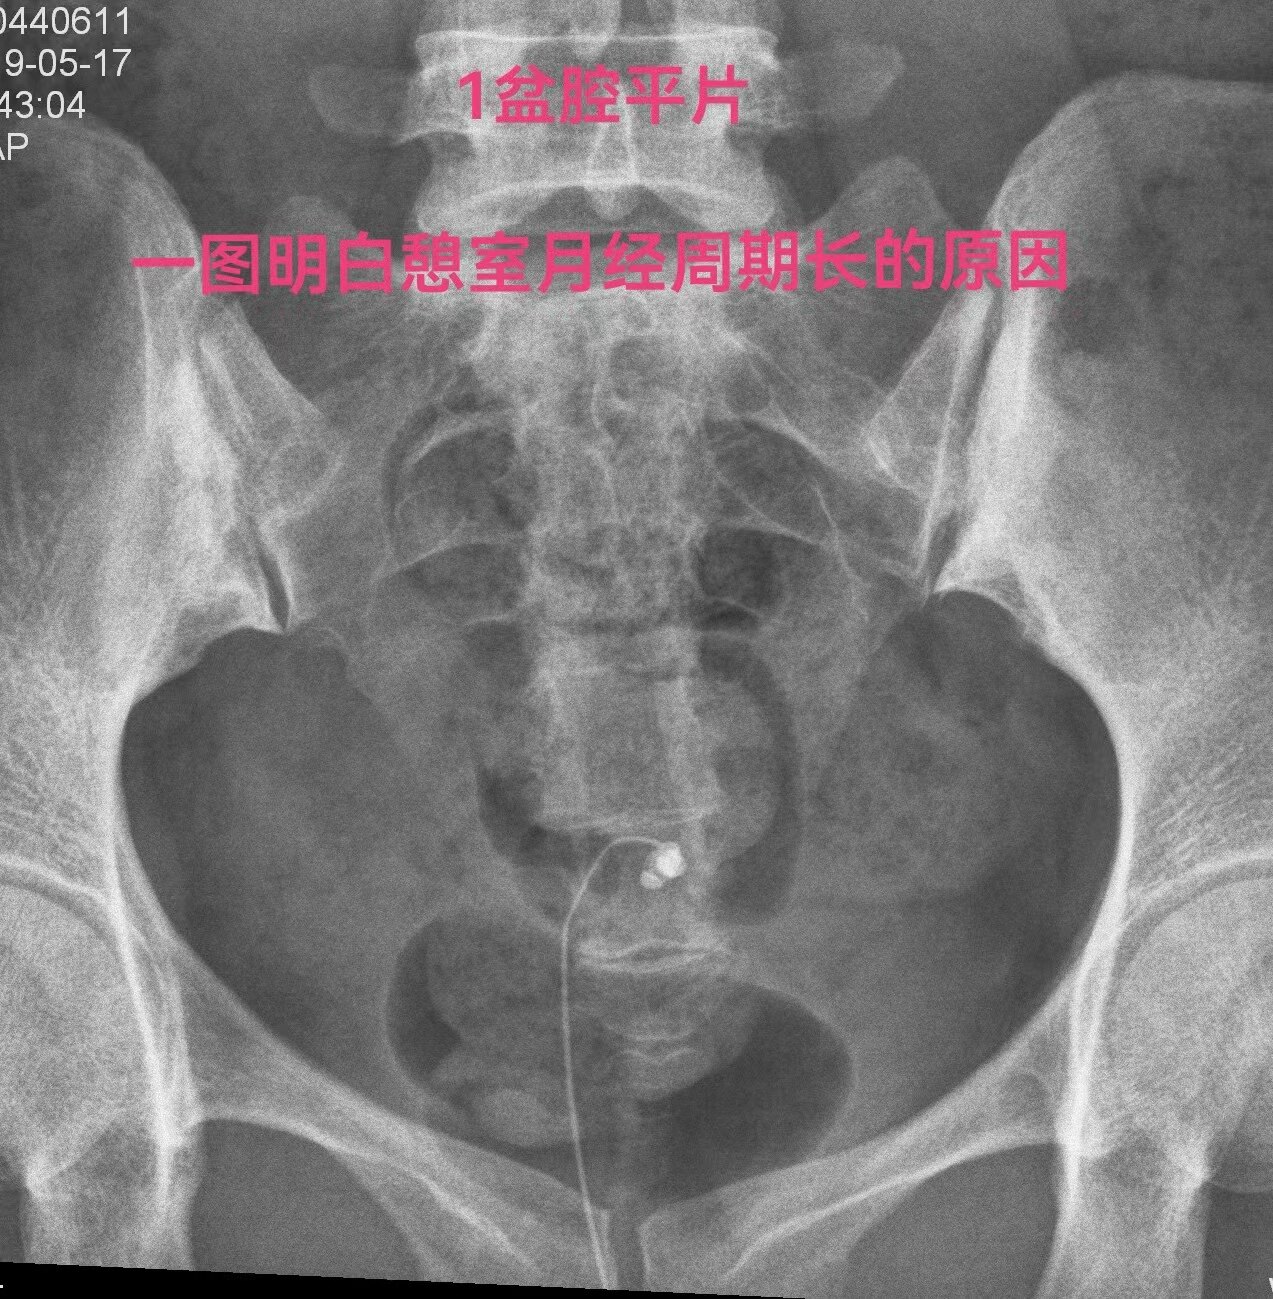

下面一例造影图就可以看直观看懂憩室导致经血流出不畅

1.jpg